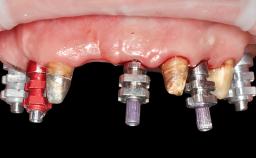

A 65-year-old female patient was referred to our clinic by another patient for evaluation and treatment of her compromised dental clinical situation. The patient presented with a pessimistic attitude and declared she had no confidence in the possibility of improving her oral situation. Her main complaint was discomfort, inability to chew, and collapse of the facial tissues related to her medical history. The patient had a serious domestic accident 18 months before the consultation and suffered from a head injury, followed by 4 months in a coma. She then gradually progressed toward almost complete neurological recovery, although, at the time of the consultation, she still had difficulty walking. The patient suffered a mandibular fracture in that accident, but because her life had been in danger, the fracture had been ignored. Since the patient was immobilized at the hospital for 4 months, the mandibular fracture had healed spontaneously, but the fragments reossified in an incorrect position, which resulted in a complete discrepancy between the positions of the remaining mandibular teeth and the maxillary teeth